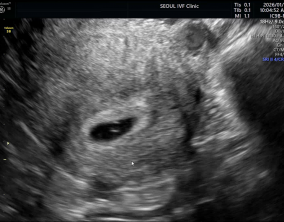

임신 수치 16, 9주차 기적의 기록

서울IVF에서는 단순히 배아 생성과 이식만 해주시는 것이 아니라, 제 생활 전반까지 신경 써주셨습니다. 휴식기에도 그저 기다리는 것이 아니라 항노화에 도움이 되는 링겔을 처방…